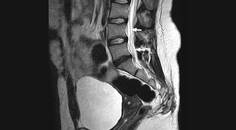

Diagnostic & Treatment Delay in Temporal Lobe Epilepsy

Rajarshi Mazumder, MD; Jessica Pasqua, MDRajarshi Mazumder, MD; Jessica Pasqua, MD - Imaging & Testing